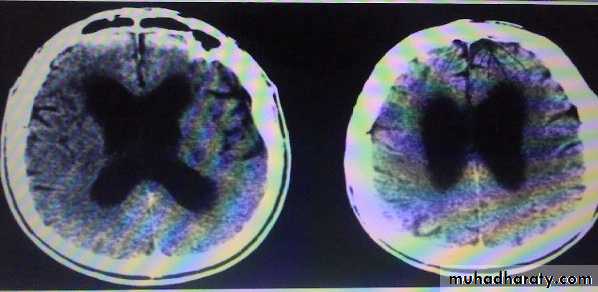

consisting of an abnormal gait (ataxic or apractic), dementia (usually mild to moderate), and urinary incontinence.

Neuroimaging findings in NPH are those of a communicating (non-obstructive) hydrocephalus with a patent aqueduct of Sylvius. In many cases periventricular edema is present. There is no evidence of cortical or hippocampal atrophy.

The indolent nature of the process results in enlarged lateral ventricles but relatively little increase in CSF pressure.

Treatment by ventriculoatrial, ventriculoperitoneal, or lumboperitoneal shunting surgery.